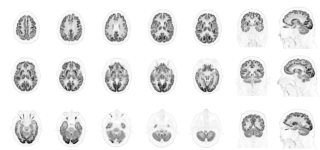

Dr. Rosa-Neto’s project will leverage and enhance existing infrastructure at the McConnell Brain Imaging Centre (BIC) of The Neuro by acquiring a new Panorama GS tomograph from United Imaging—the first ultra-high-sensitivity whole body PET/CT scanner in Canada.

The Panorama will aid the discovery of the next generation of Alzheimer’s biomarkers, with a particular focus on neuroinflammation—a key driver of cognitive decline in neurodegenerative conditions. This work holds the promise of transforming Alzheimer’s research and care, enabling earlier diagnosis, more precise disease progression monitoring, and the development of personalized therapies. Ultimately, these innovations could lead to improved outcomes and quality of life for the growing number of Canadians affected by Alzheimer’s disease.